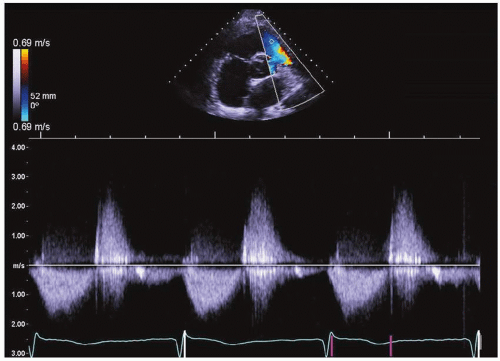

17. Continuous-wave Doppler at the pulmonic valve in a 42-year-old woman with right ventricular dilatation (Fig. 28-3). Which of the following findings by itself can establish the definitive diagnosis?

View Answer

17. Answer: A. The patient has a wide regurgitant jet of pulmonic regurgitation (PR) by color Doppler and normal right ventricular systolic function with normal cardiac output. Spectral Doppler with a short deceleration time of PR may also occur due to an abnormally elevated right ventricular end-diastolic pressure. A wide color Doppler jet can differentiate severe pulmonic regurgitation from a nonsignificant regurgitant lesion. Normal RV systolic function with normal cardiac output in the presence of a short PR deceleration time supports the diagnosis of severe PR as opposed to a noncompliant RV. A noncompliant RV typically occurs in patients with an enlarged RV with reduced systolic function.